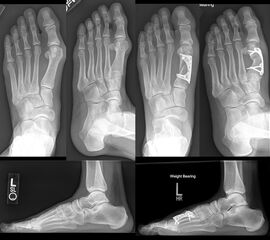

Zum Lesen der Bildbeschreibung und zur Vollansicht bitte das Bild anklicken. Bild: Amol Saxena.

Diaphysäre Osteotomien können mit einer Akin-Osteotomie kombiniert werden, zur gleichzeitigen Korrektur eines Hallux valgus interphalangeus und zur Zentrierung der Strecksehne über dem Drehpunkt des Großzehengrundgelenks.

Zum Lesen der Bildbeschreibung und zur Vollansicht bitte das Bild anklicken. Bild: Markus Walther.

Die eigenständige Bewegung und Mobilisation im Großzehengrundgelenk und Interphalangealgelenk kann durch Physiotherapie, Lymphdrainage und Gangschule unterstütz werden. Eine radiologische Kontrolle erfolgt zur Dokumentation des Operationsergebnisses intraoperativ und nach 6 Wochen im Konfektionsschuh.